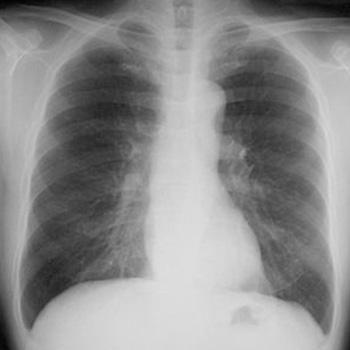

医療の分野では、放射線を使用した検査として、レントゲン検査・胃バリウム検査・CT検査・マンモグラフィ検査などがあります。